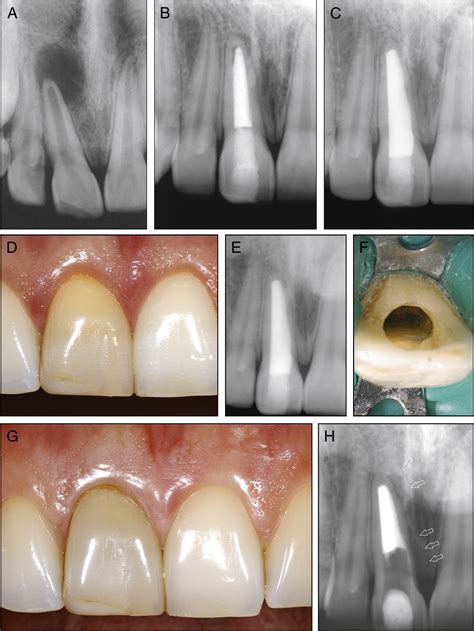

Endodontic Surgery Explained - Riverbend Endodontics